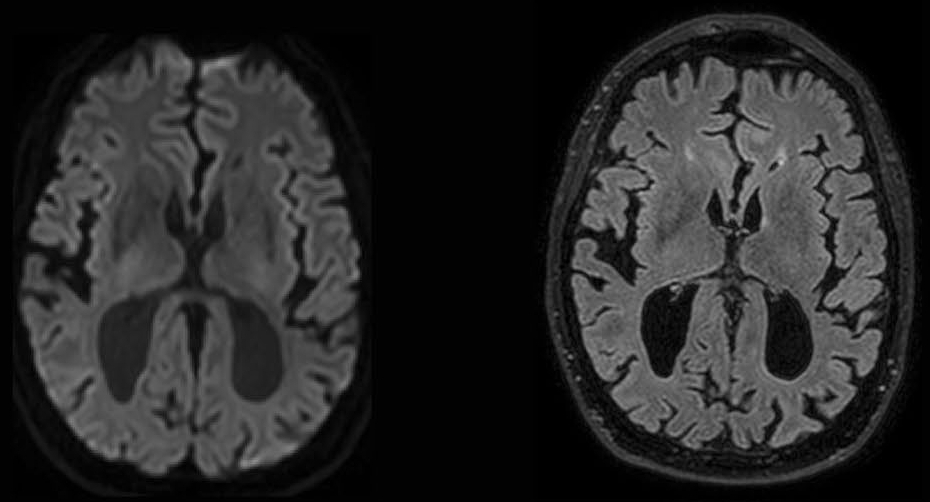

Comatose patients after cardiac arrest have an uncertain prognosis. In about half of all, hypoxic brain damage precludes recovery of consciousness. Early predictors of functional recovery can prevent futile continuation of intensive care treatment. With the current recommended predictors, including neurological examination, EEG, SSEP, and NSE blood levels, a reliable prognosis is possible in about half of all patients. New, complementary predictors are needed.

The Cracking Coma study is a longitudinal multicenter cohort study to establish the additional predictive value of various MRI techniques and derive multimodal prediction models to optimize outcome prediction. Candidate MRI factors include diffusion (DWI, DTI) and resting state functional MRI measures. The study protocol can be found here.